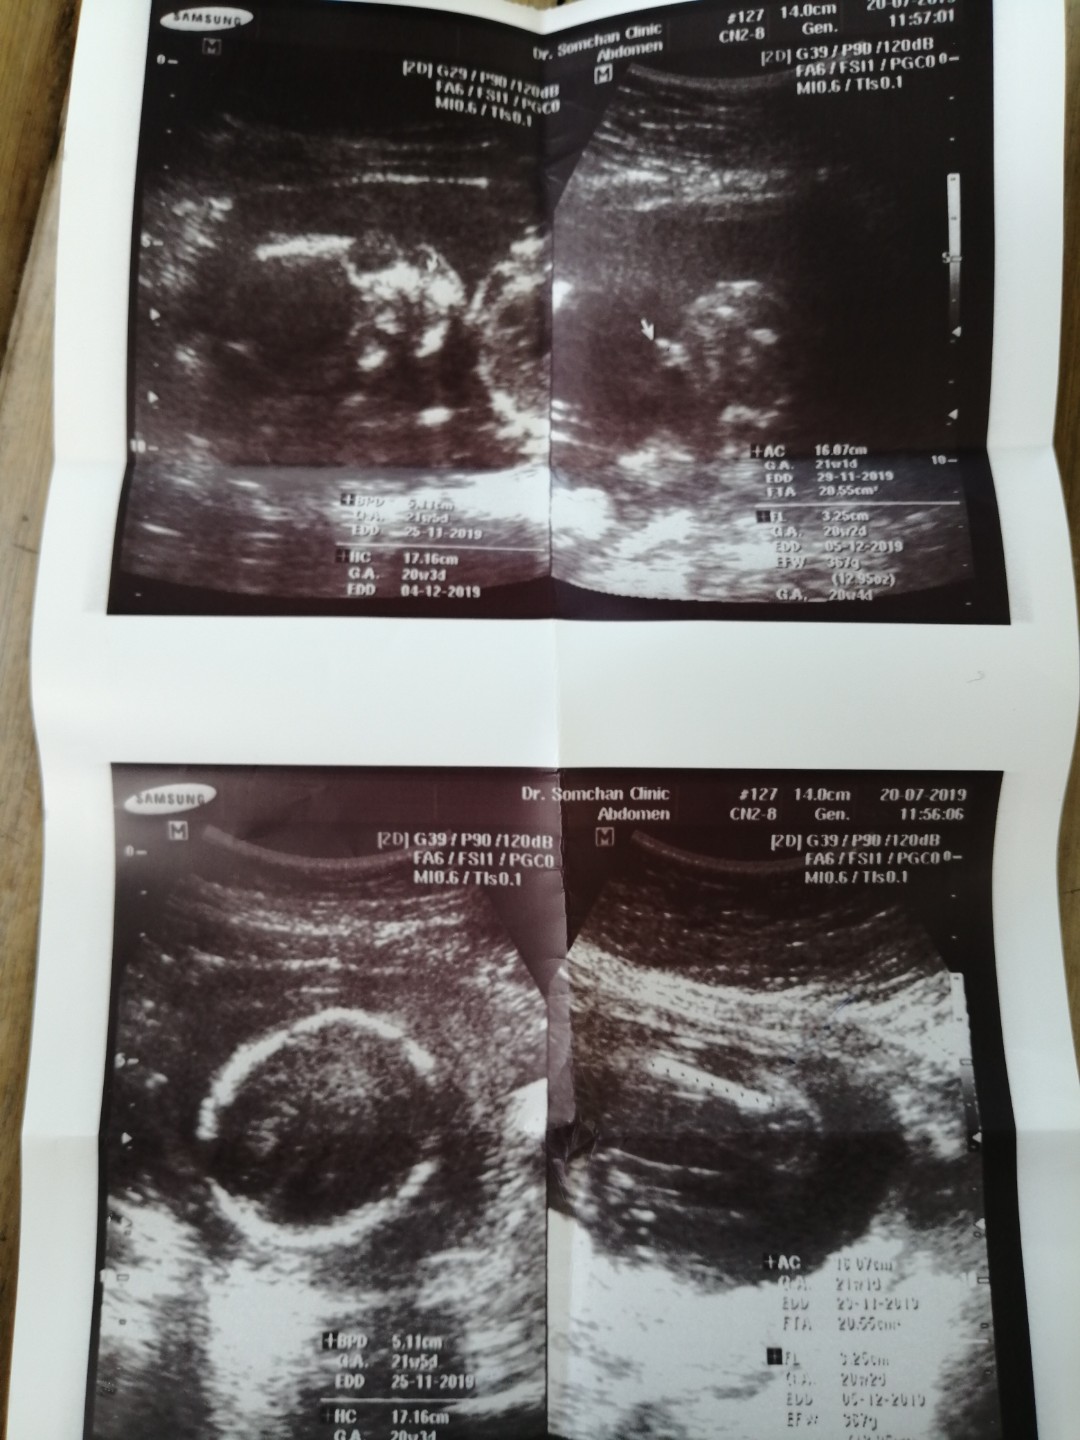

ในภาพเป็น ผช ใช่ไหมค่ะ พอดีหมอขอชัวร์ๆ เดือนหน้า เลยสอบถามแม่ๆ ที่มีประสบการณ์ลูกชาย หน่อยค่ะ ?ขอดูใบอัตตลาซาวเด็ก ผช . หน่อยจร้าาา? ถาพไม่ชัดเพราะถ่าย VDO มาจร้า ??